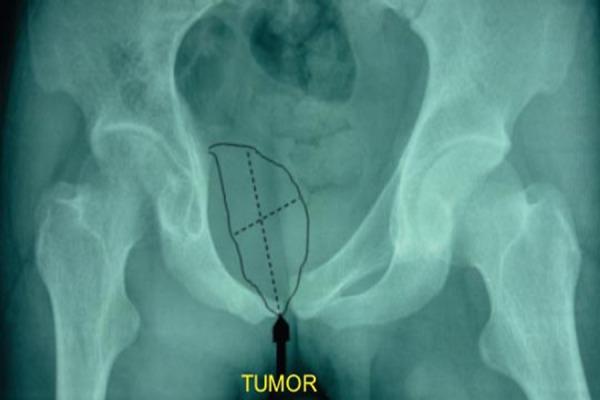

We present a case of a 21 year old male who presented with a swelling of the right inguinal region which was gradually progressive. Radiologically, there was a lytic expansile lesion of the superior pubic ramus. A contrast computed tomography revealed multiloculated cystic cavities and histopathology confirmed the diagnosis of ABC. Surgical excision of the complete tumor by anterior approach was done. Till date (2 years since surgery) patient has no recurrence.

我们报告一例21岁男性患者,其右腹股沟区出现逐渐增大的肿胀。影像学检查显示耻骨上支有溶骨性膨胀性病变。增强计算机断层扫描显示多房性囊腔,组织病理学确诊为动脉瘤样骨囊肿。通过前路完整切除肿瘤。截至目前(手术后2年),患者无复发。